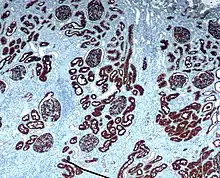

Chromogenic immunohistochemistry of a normal kidney targeting the protein CD10.

IHC is an excellent detection technique and has the tremendous advantage of being able to show exactly where a given protein is located within the tissue examined. It is also an effective way to examine the tissues. This has made it a widely used technique in neuroscience, enabling researchers to examine protein expression within specific brain structures. Its major disadvantage is that, unlike immunoblotting techniques where staining is checked against a molecular weight ladder, it is impossible to show in IHC that the staining corresponds with the protein of interest. For this reason, primary antibodies must be well-validated in a Western Blot or similar procedure. The technique is even more widely used in diagnostic surgical pathology for immunophenotyping tumors (e.g. immunostaining for e-cadherin to differentiate between DCIS (ductal carcinoma in situ: stains positive) and LCIS (lobular carcinoma in situ: does not stain positive)[11]). More recently, immunohistochemical techniques have been useful in differential diagnoses of multiple forms of salivary gland, head, and neck carcinomas.[12]